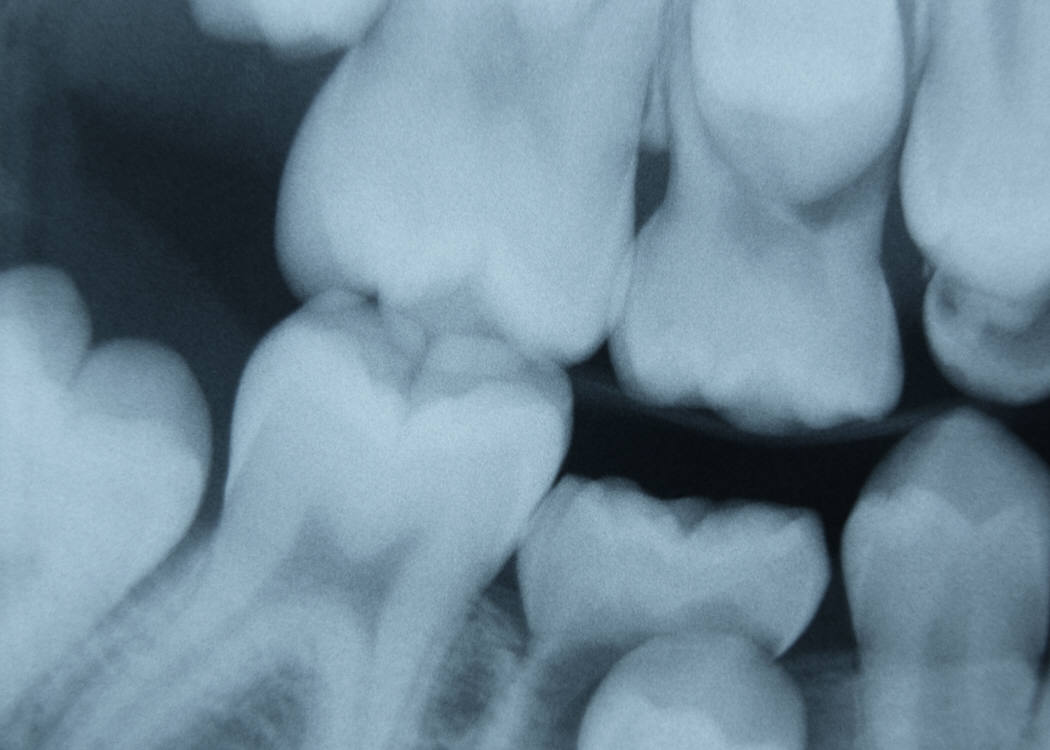

I had this major dental appointment today, and really, it wasn’t so much having the work done as it was thinking about the work. Because a vivid imagination might be a wonderful thing when one is writing zany Once upon a times, but when one uses that same imagination to obsess over everything that can go wrong whilst sitting in a dentist’s chair, it’s kinda scary. I mean, I know that all my teeth are not going to fall out. I know that worms can’t possibly exist for 37 years beneath a crowned tooth. That my dentist is NOT going to accidentally cut off half my tongue. I know all that. But still.